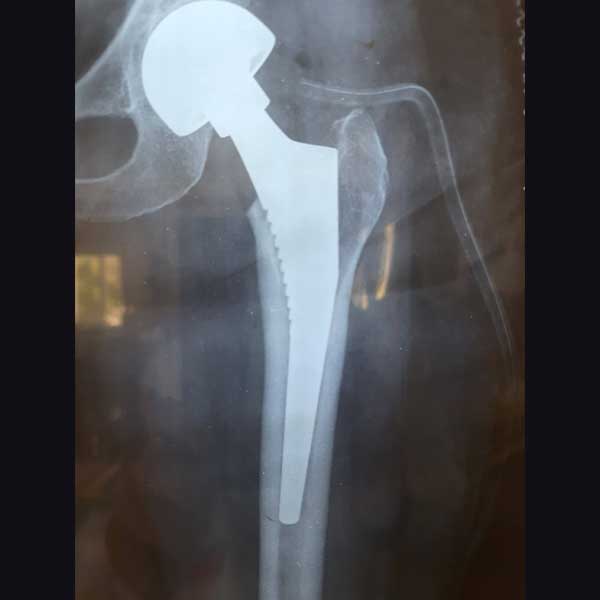

Case 1 - Hip Hemiarthroplasty

A female patient, aged 72 years. She had been diagnosed to have a Closed fracture of neck Fracture. She was treated operatively with Hip Hemiarthroplasty.

Post-operative